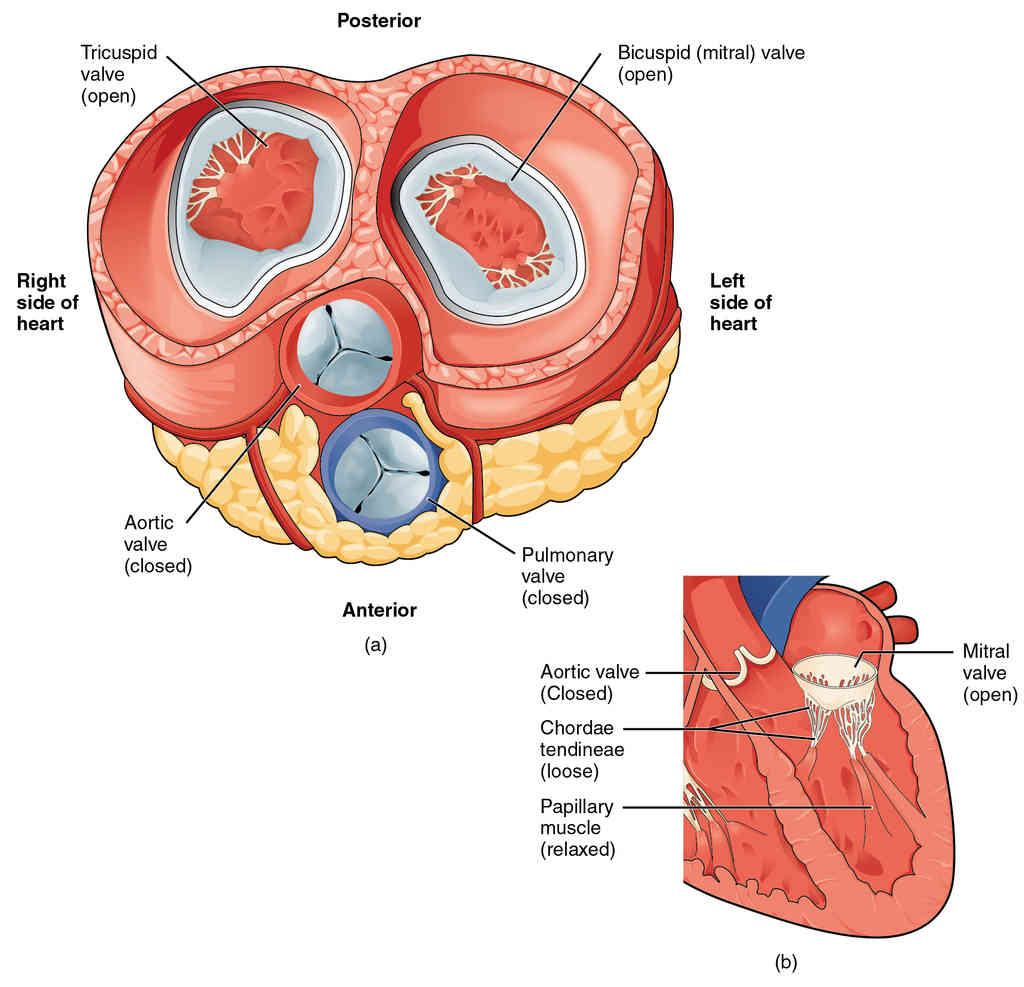

This page is under construction. For now, it is just a resource of the images found in the OpenStax Anatomy and Physiology Handbook. It wil slowly change into a revision tool. Each slide has a number. Use this to refer to the slide. When completed, it will have an unlabelled section, with labelled slides in parallel. On the unlabelled slides, write your answer and use the labelled slide to assess yourself. Keep track by also noting the number on each slide. Improvement at each attempt is important, more so than full marks on a first attempt.